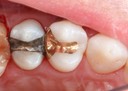

Alan Chinn #20 pre-op

Alan Chinn #20 caries removal